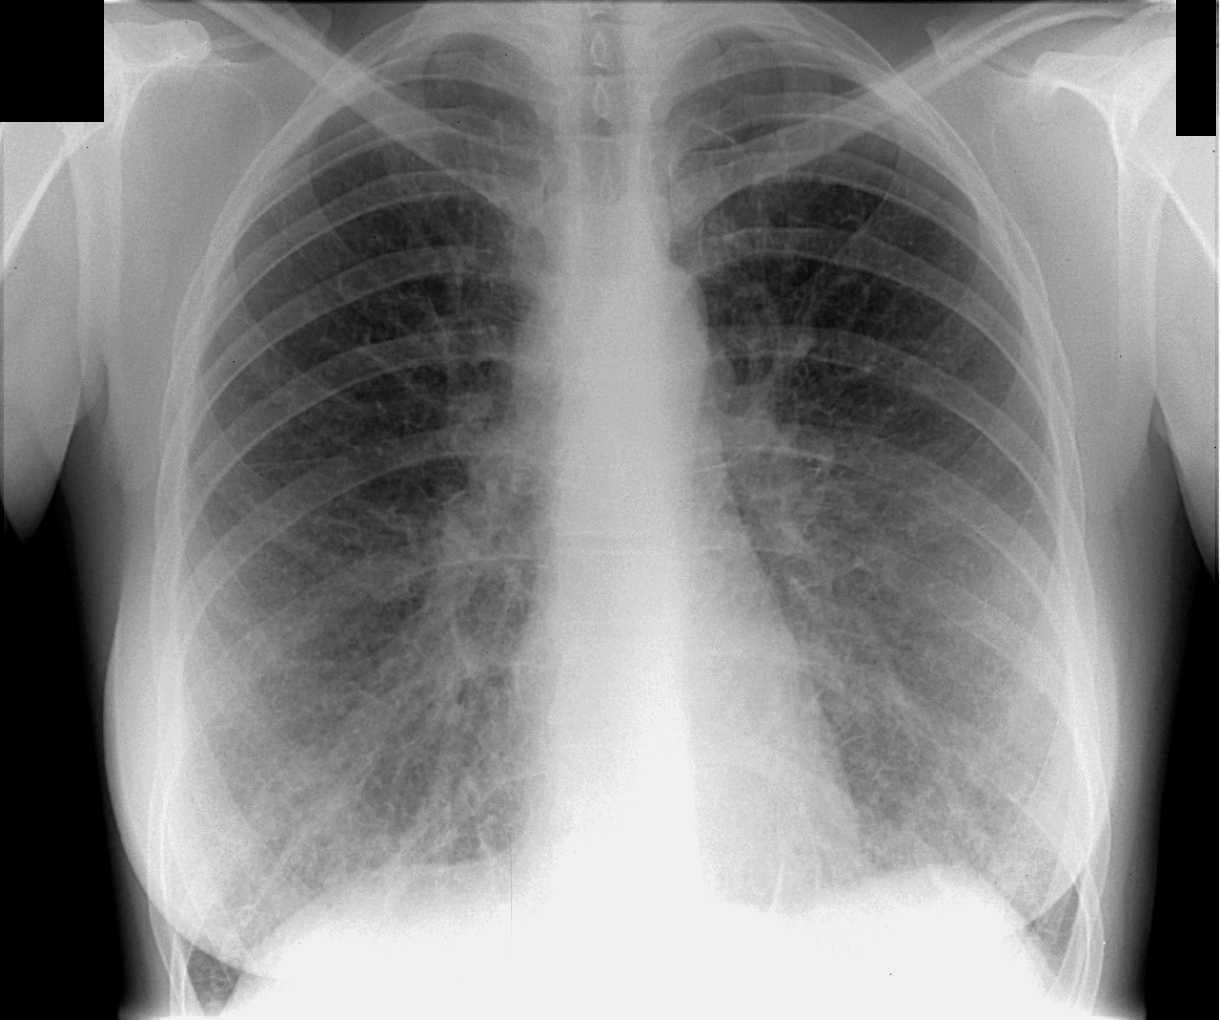

Фотографии рентгеновских снимков без необходимости направления от врача